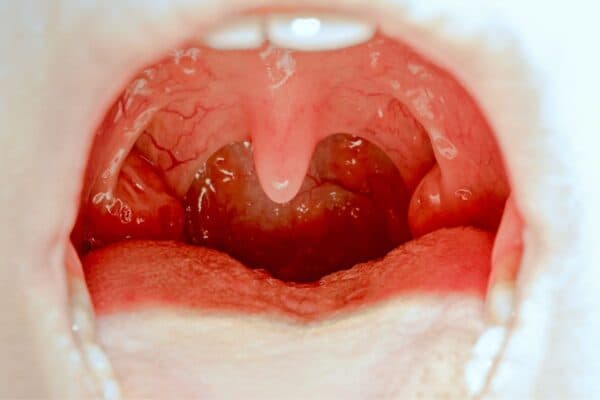

Amidan là tổ chức lympho có vai trò chống nhiễm trùng và ngăn ngừa tác nhân có hại tấn công, gây bệnh cho cơ quan họng của cơ thể. Khi bị tấn công quá mức, khiến amidan không thể chống lại thì sẽ dẫn tới tình trạng nhiễm trùng, còn được gọi là viêm amidan.

Viêm amidan có thể xảy ra ở bất kỳ đối tượng nào nhưng thường phổ biến ở trẻ nhỏ do sức đề kháng kém. Bệnh gây ra các triệu chứng khó chịu cho người bệnh như: Sưng tấy amidan, đau rát họng, sốt cao, khó thở, nuốt vướng… Nếu không điều trị, viêm amidan còn có thể dẫn tới các biến chứng có hại đối với sức khỏe của mọi người.

Tác nhân chính gây ra tình trạng viêm amidan thường là do vi khuẩn, virus… Chúng trú ngụ trong các khe, hốc của amidan và lợi dụng lúc sức đề kháng của cơ thể giảm sút rồi tấn công và gây bệnh. Viêm amidan cấp tính thường biểu hiện rõ và tiến triển trong khoảng từ 1-2 tuần. Nếu không điều trị kịp thời, viêm nhiễm kéo dài có thể dẫn tới viêm amidan mạn tính, viêm amidan quá phát…

Viêm amidan là tình trạng viêm nhiễm tổ chức lympho ở cổ họng